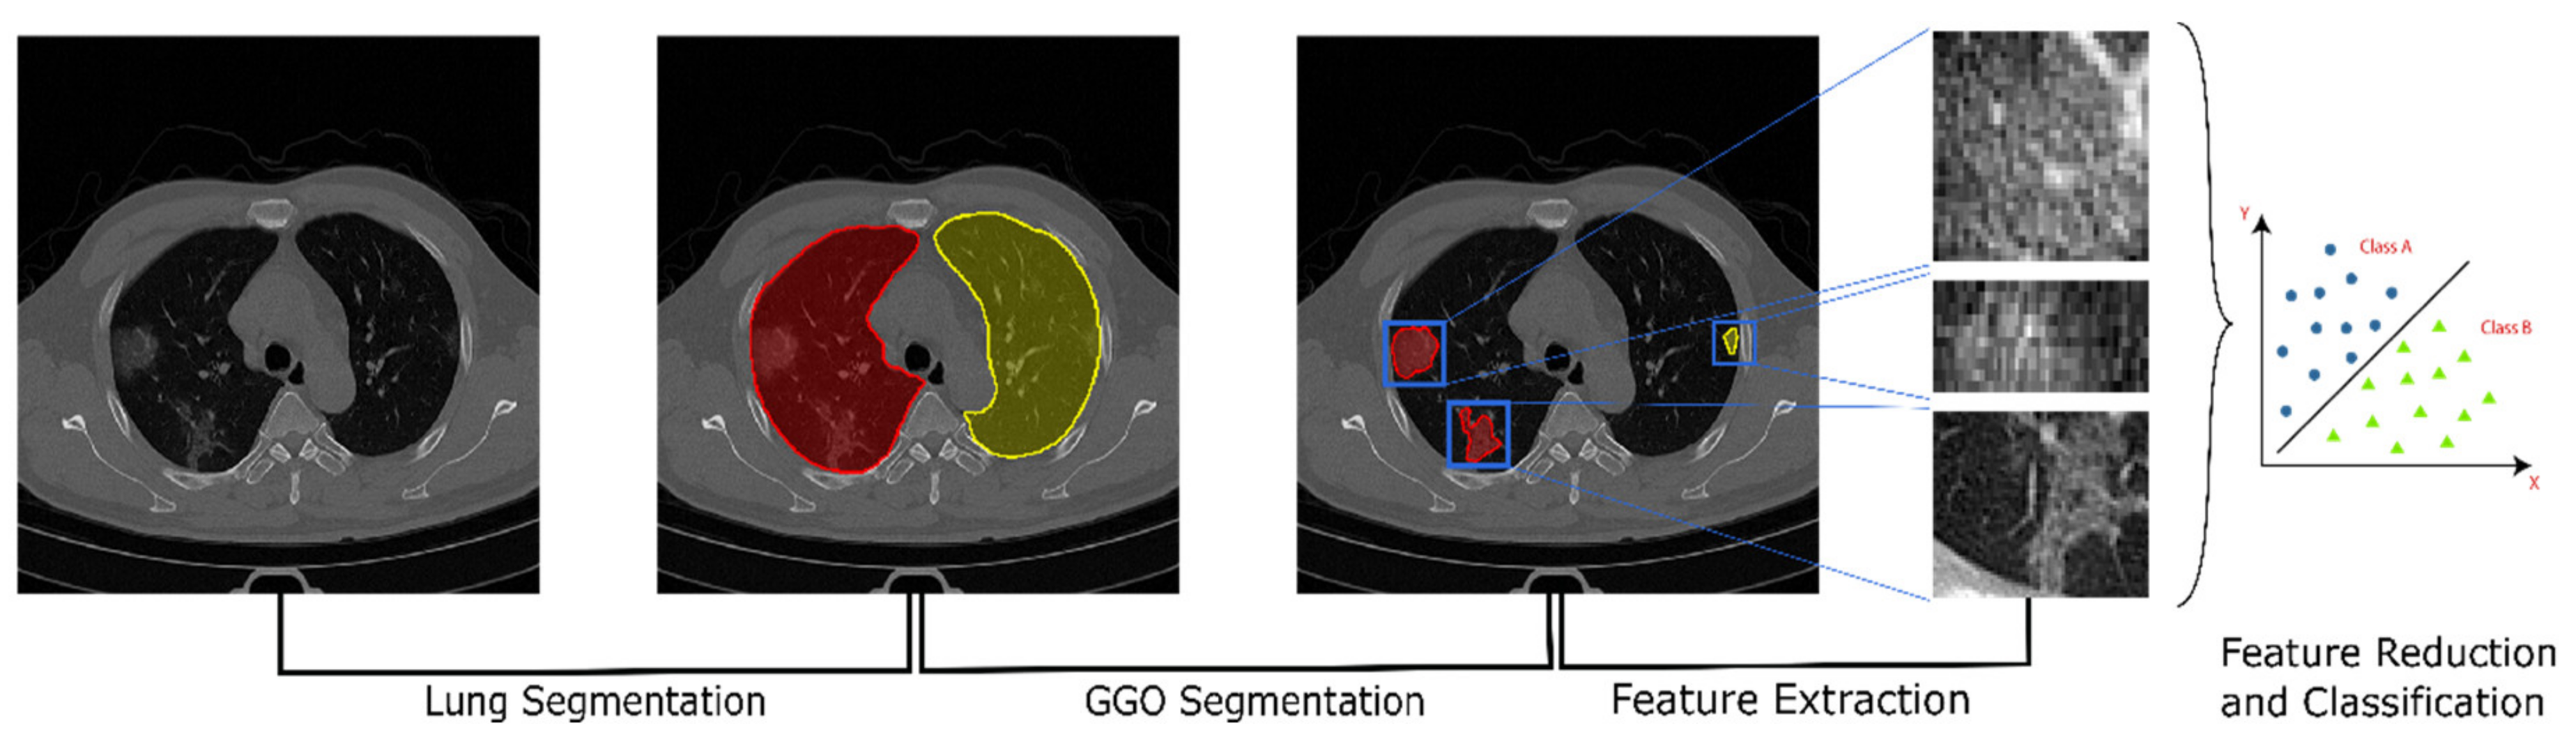

2.2. Pipeline Overview

The workflow developed in this work as show in Figure 1 can be split into 3 steps: (1) the segmentation of the lungs; (2) segmentation of the GGO areas; (3) estimation of the radiomic features.

Figure 1. A schematic representation of the proposed pipeline. From the left: raw CT scan; segmentation of the two lungs using a pre-trained U-Net model; segmentation of the GGO areas using k-means clustering; extraction of radiomic and Haralick features; classification and prediction of the clinical characteristics and outcomes.